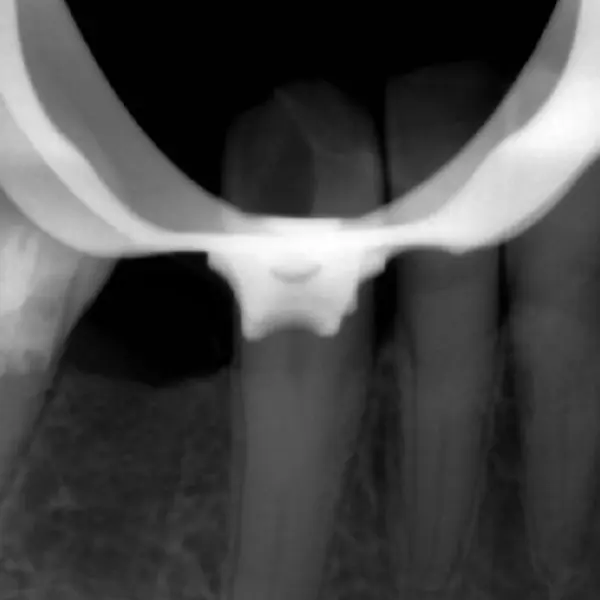

Создание прохода:

- Файл 25.02: после предварительной обработки ультразвуком, этот гибкий файл позволил создать “байпасс” – безопасный проход через сложный, облитерированный участок.